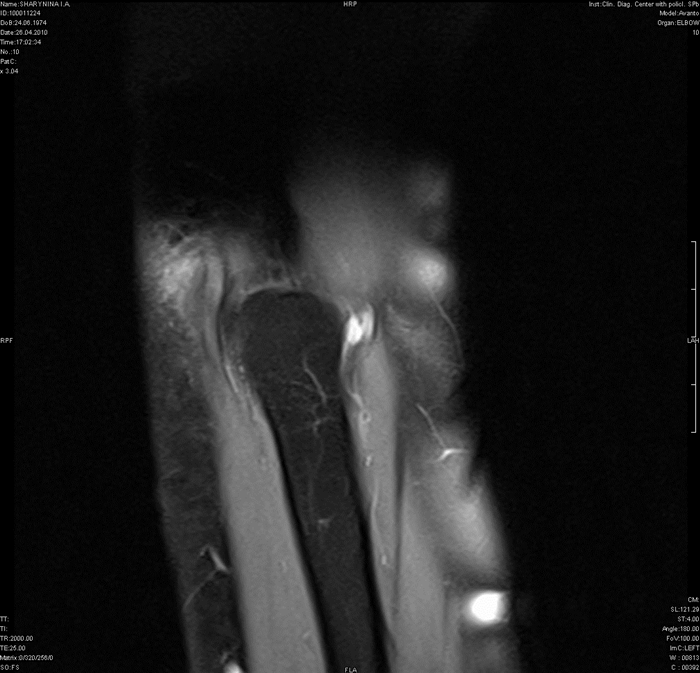

МРТ-артрограмма при повреждении лучевой коллатеральной связки

а) Терминология:

1. Синоним:

• Лучевая коллатеральная связка (ЛуКС) также называется латеральной коллатеральной связкой (ЛКС)

2. Определение:

• Состоит из двух компонентов: ЛуКС и латеральной ЛоКС, также известной как лучелоктевая связка (ЛЛоКС)

б) Визуализация:

1. Общая характеристика:

• Лучший диагностический критерий:

о Распространение контрастного препарата через дефект в связке

• Локализация:

о ЛуКС отходит от латерального надмыщелка к кольцевой связке головки лучевой кости:

- Разрыв обычно возникает в начале связки, реже - в конце

о ЛЛоКС отходит от заднего края латерального надмыщелка к гребню супинатора локтевой кости:

- Разрыв обычно возникает в средней трети/начале связки

2. Рекомендации по визуализации:

• Лучший метод визуализации:

о МР-артрография:

- Позволяет выявлять отек костного мозга и патологические изменения мышц, которые при КТ не визуализируются

• Рекомендации по выбору протокола:

о Рука полностью разогнута в локтевом суставе, супинирована

о Коронарная плоскость: на аксиальной томограмме строится через середину отрезка, соединяющего медиальный и латеральный мыщелки плечевой кости:

- Коронарные срезы: в режиме Т1, а также Т2 с подавлением сигнала от жировой ткани

- Часто полезным оказывается режим GRE

о Аксиальные срезы: в режиме протонной плотности с подавлением сигнала от жировой ткани (PD FS)

о Сагиттальные срезы: в режиме PD FS

(Слева) МР-артрография в режиме Т2ВИ FSE FS, коронарный срез: визуализируются дегенеративный разрыв ЛуКС и отрыв сухожилия разгибателя вследствие выраженного эпикондили-та.

(Справа) МР-артрография в режиме Т2ВИ FS, коронарный срез: отмечаются поел едав и я вывиха - разрыв лучевой и локтевой коллатеральных связок, а также сухожилий разгибателей и сгибателей в месте их отхождения.